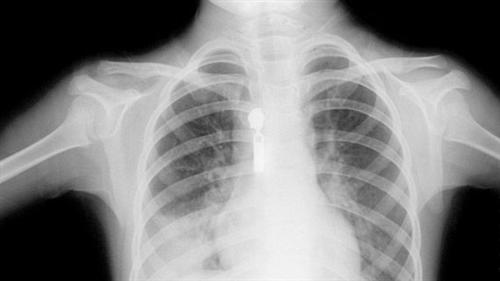

相关图片